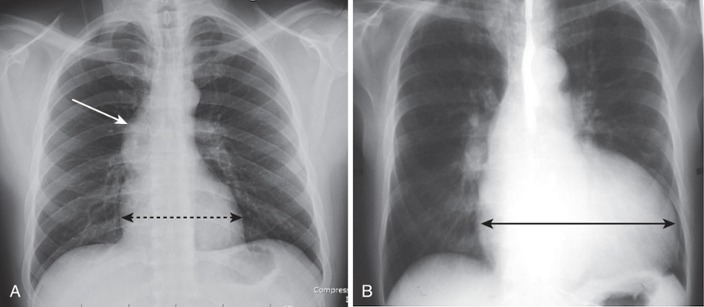

Airspace Disease (pneumonia)

Frontal and lateral views of the chest demonstrate airspace disease on the lateral film (B) in the right lower lobe (white arrow) that may not be immediately apparent on the frontal film (you can see the pneumonia in the right lower lobe in [A] [black arrow]).

In this case, a right lower lobe pneumonia superimposed on the lower spine on the lateral view makes the spine appear “whiter” (more dense) just above the diaphragm. This is called the spine sign.